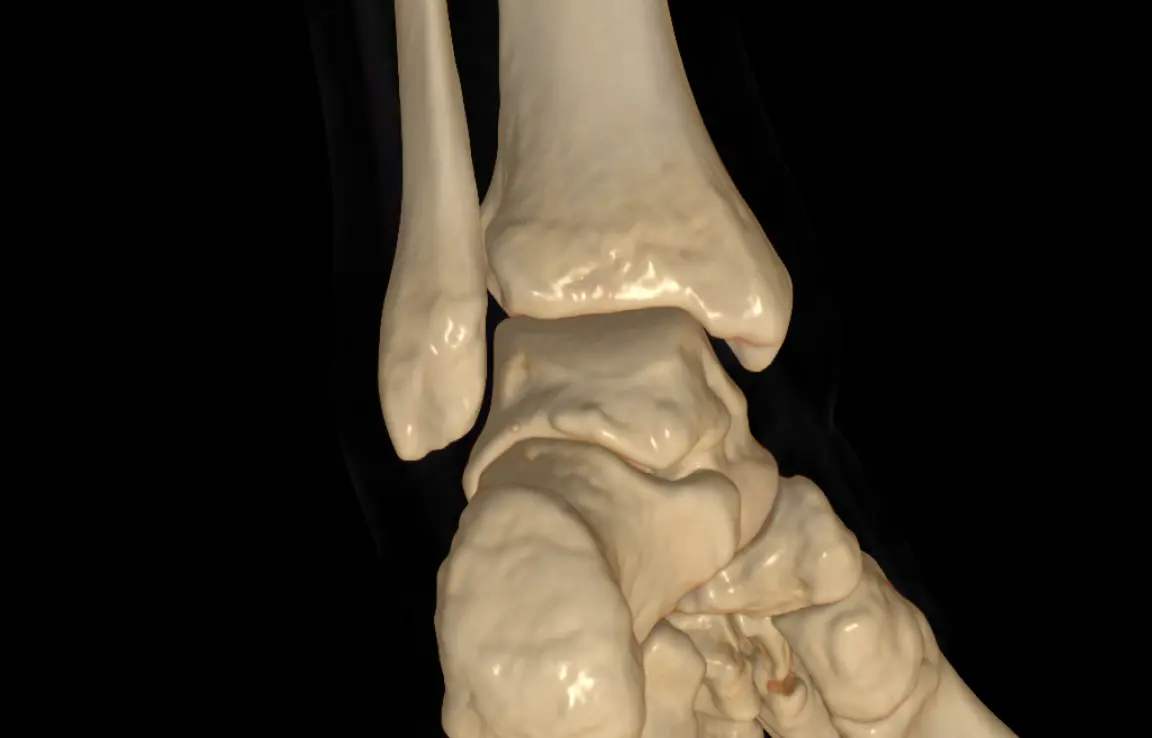

Zum Glück legte meine Freundin bei ihrem Hausarzt ein gutes Wort für mich ein. Also ging es am Montag zunächst in die Praxis, dann zur Radiologie: erst Röntgen, zurück zur Praxis, anschließend noch einmal zum CT. Die ersten Befunde ließen nichts Gutes erahnen, von einem leichten Bruch war die Rede.

Der Arzt organisierte schließlich einen Termin in der Unfallchirurgie im Krankenhaus. Eine Stunde später saß ich dort, erneut beim Röntgen. Und siehe da: Auch das Wadenbein hatte einen Knacks.

Das Gesundheitssystem funktioniert, das ist die gute Nachricht. Am Ende wurde mir schnell und effektiv geholfen. CT-Aufnahmen und andere Bilder wurden digital sofort übertragen und waren sowohl im Krankenhaus als auch beim Arzt unmittelbar verfügbar.